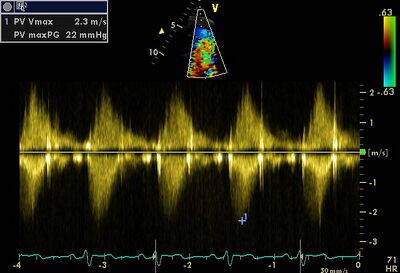

Quantification pulmonary valve stenosis

PGmax

<36 mmHg

36-64mmHg

>64 mmHg

Vmax

<3 m/s

3-4 m/s

>4 m/s